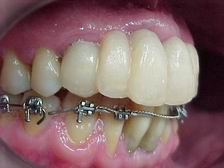

Provisórios estéticos guia anatômico VISTA LATERAL DIREITA

Provisórios estéticos (vista direita)